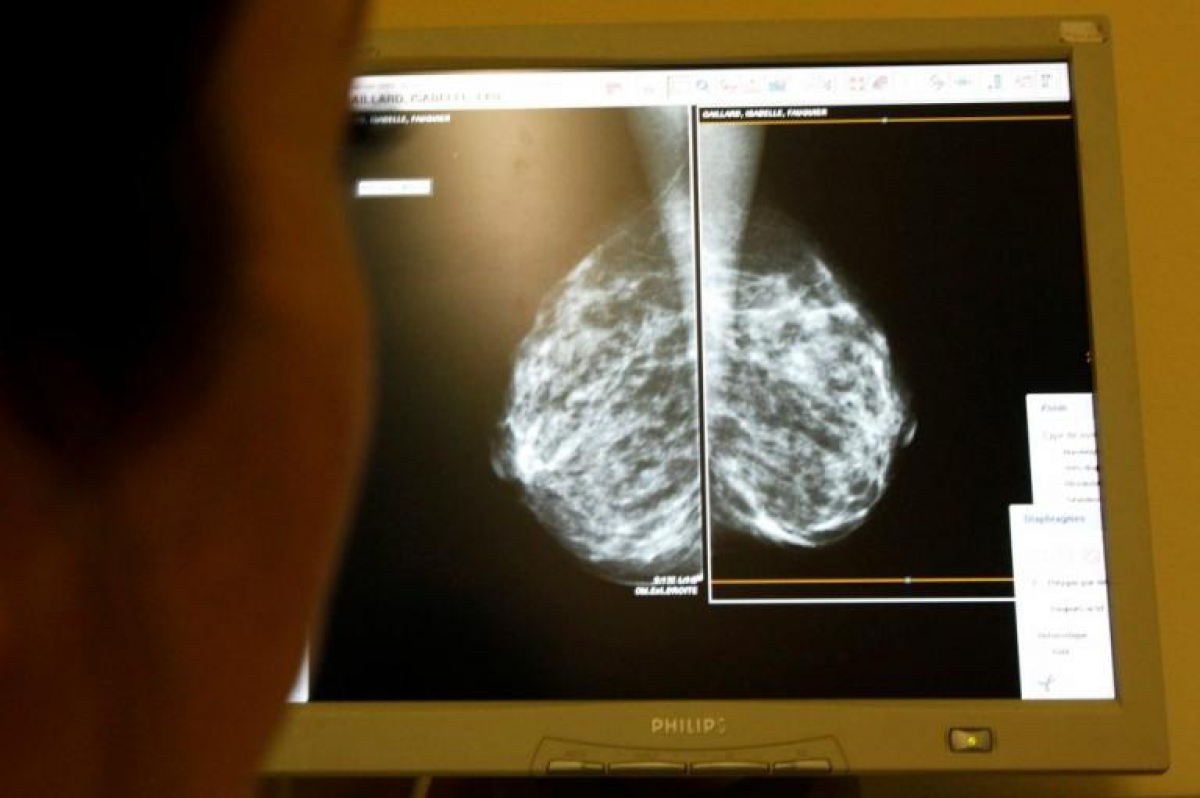

Το σύστημα υγείας στην Βρετανία προβλέπει την αποστολή πρόσκλησης για μαστογραφία σε γυναίκες ηλικίας από 50 έως 70 ετών. Η πρόσκληση αποστέλλεται κάθε τρία χρόνια. Κι αυτό, γιατί η πιθανότητα να εμφανίσουν καρκίνο του μαστού αυξάνεται όσο περνούν τα χρόνια. Για το «λάθος» «καταδικάστηκαν» οι ηλεκτρονικοί υπολογιστές αλλά οι κακές γλώσσες λένε ότι μάλλον κάποιοι έβαλαν το χεράκι τους ώστε όσες από αυτές τις γυναίκες μπορούσαν να απευθυνθούν στον ιδιωτικό τομέα…